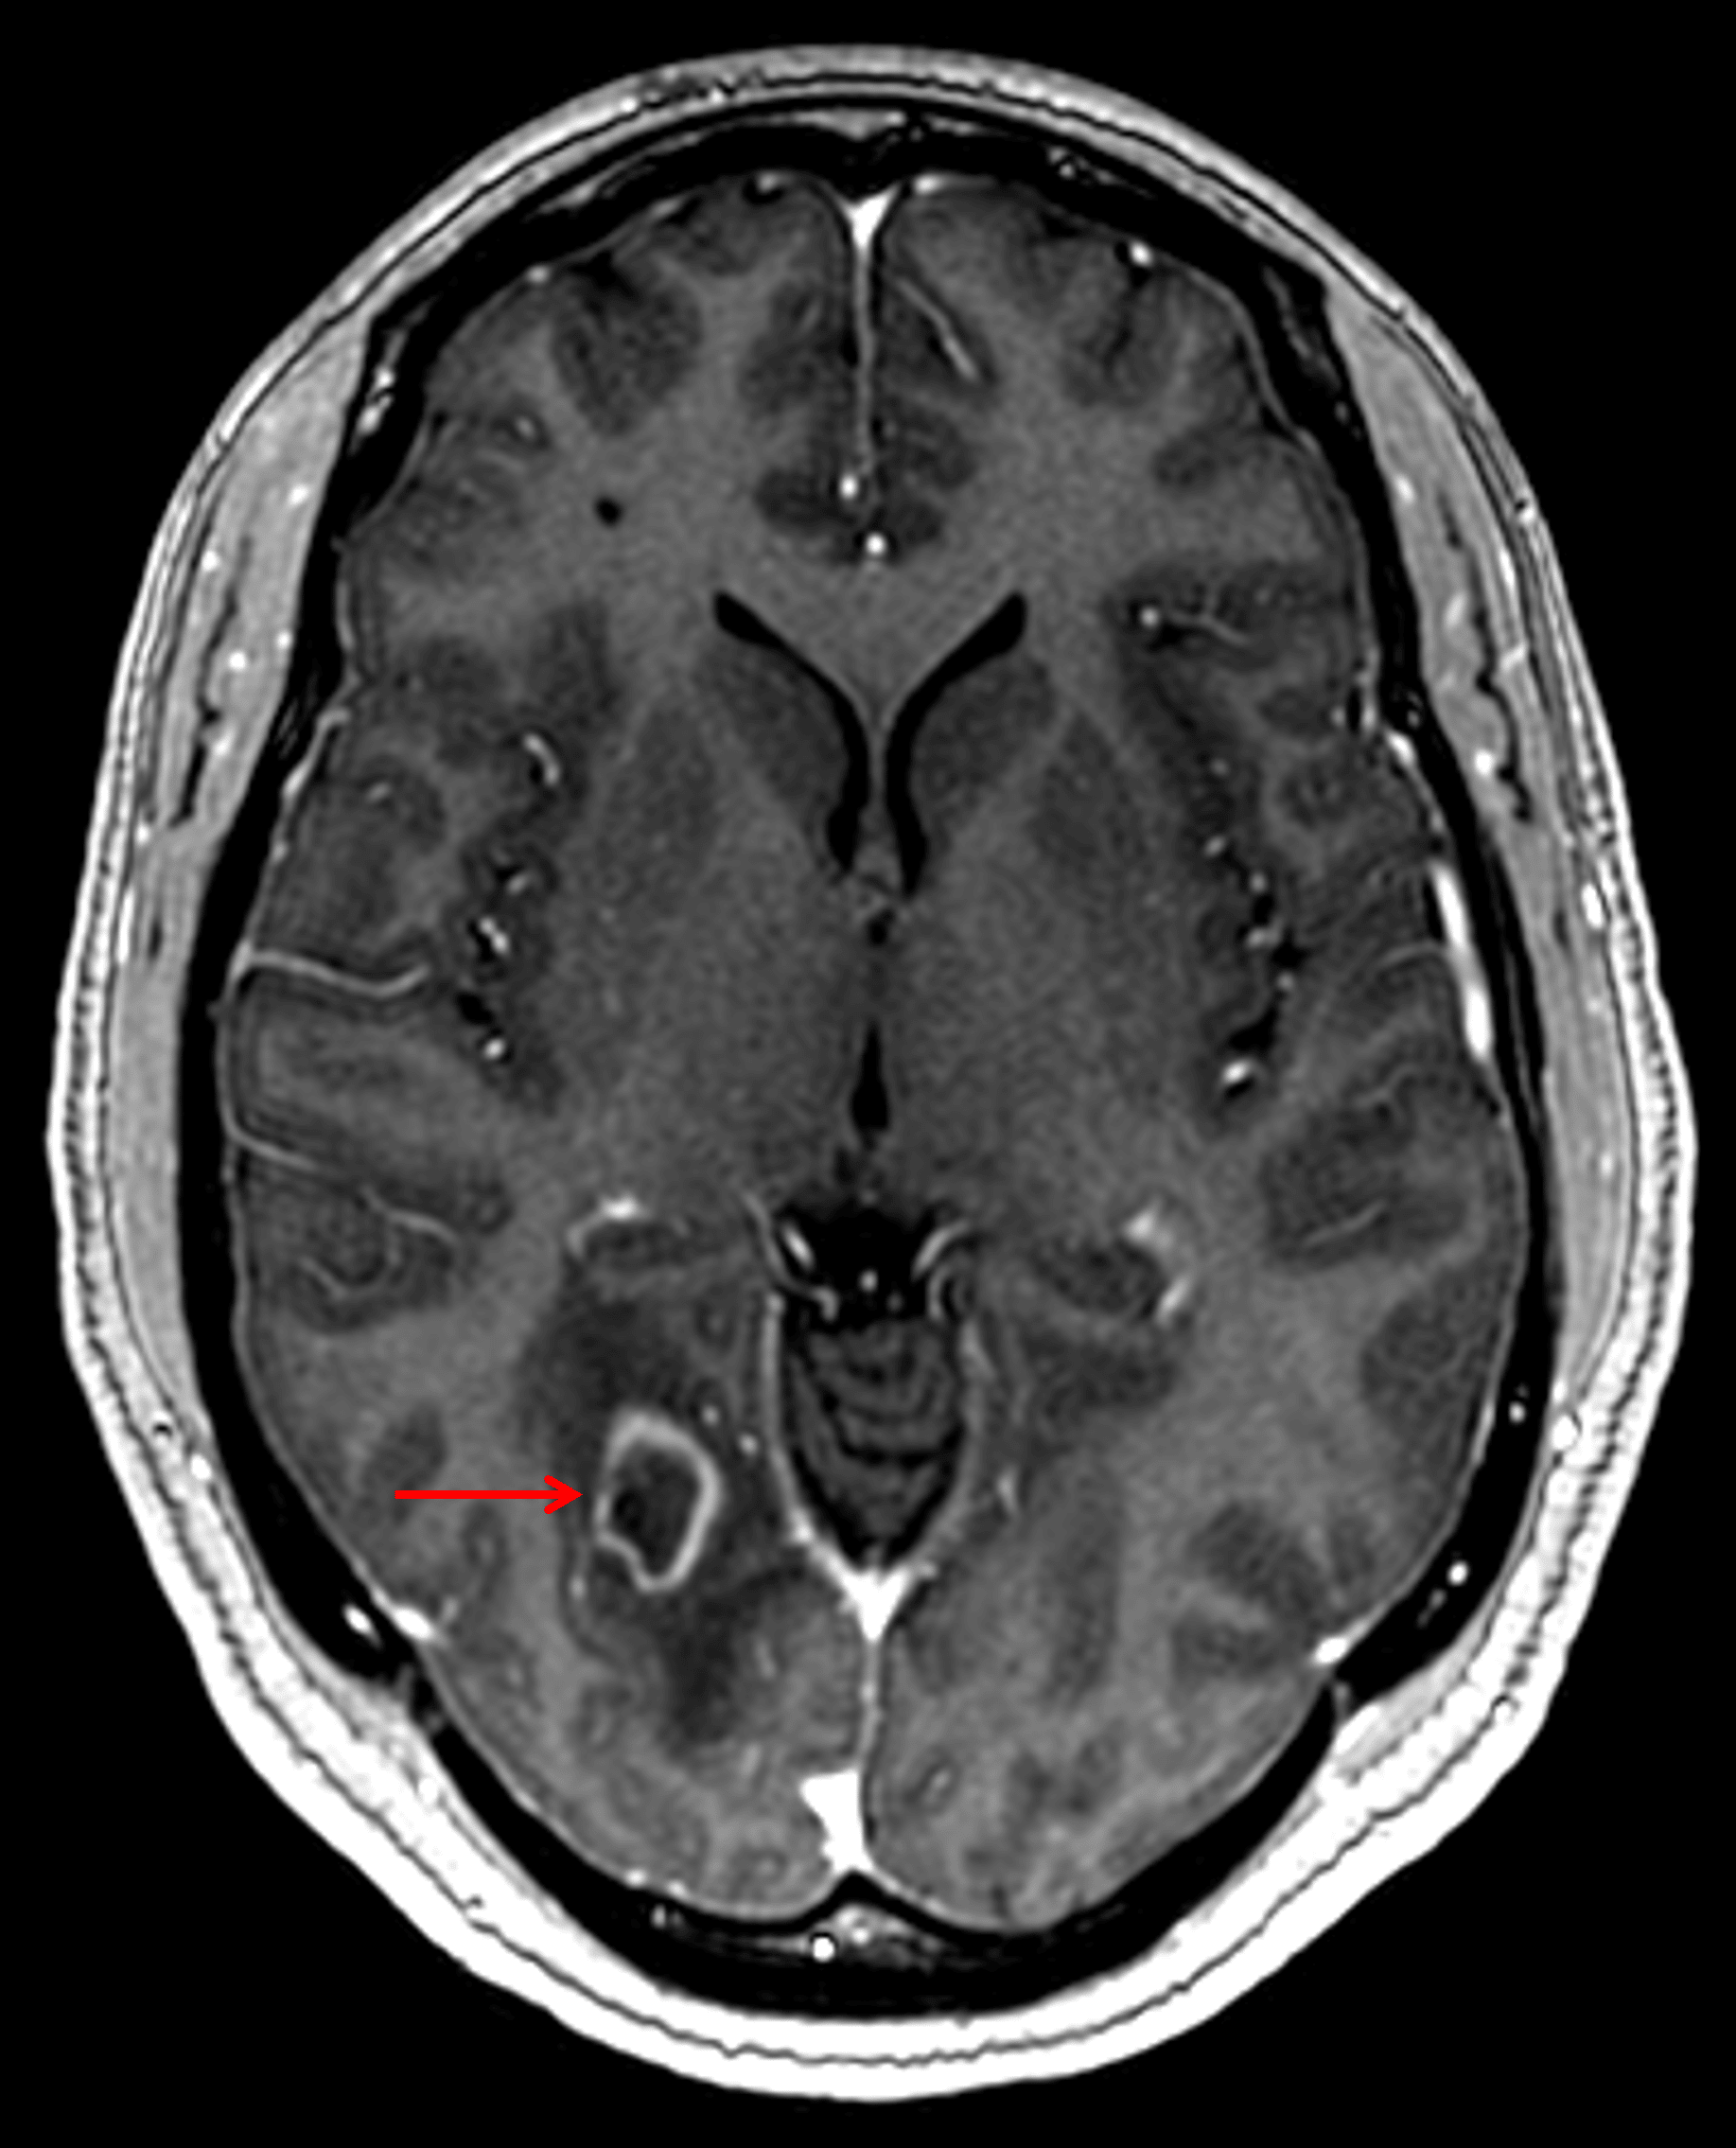

• Small area of restricted diffusion centrally in the lesion with a faint rim of restricted diffusion along the margins of the area of vasogenic edema surrounding the lesion

Faint corresponding central restricted diffusion (red arrow) as well as faint restricted diffusion along the periphery of the surrounding vasogenic edema (yellow arrows).